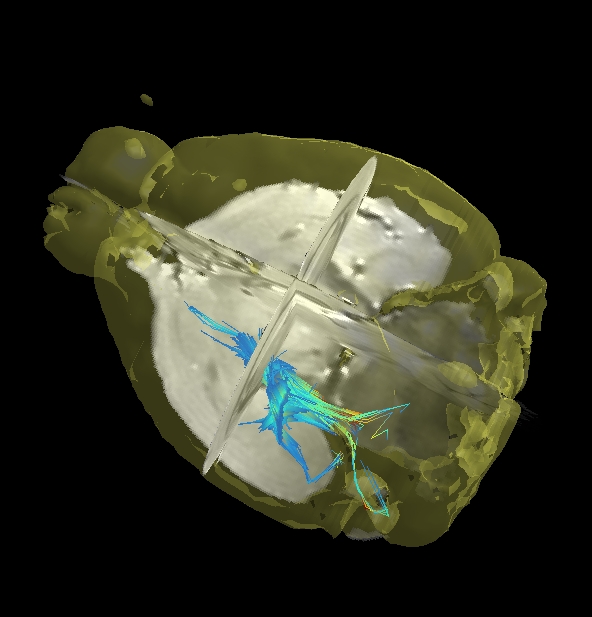

| 10.心臓解析 | 左室心筋のセグメンテーションと心臓解析 | ![]() |

| 自動化された心臓と血管の輪郭曲線のプロパゲーション | ||